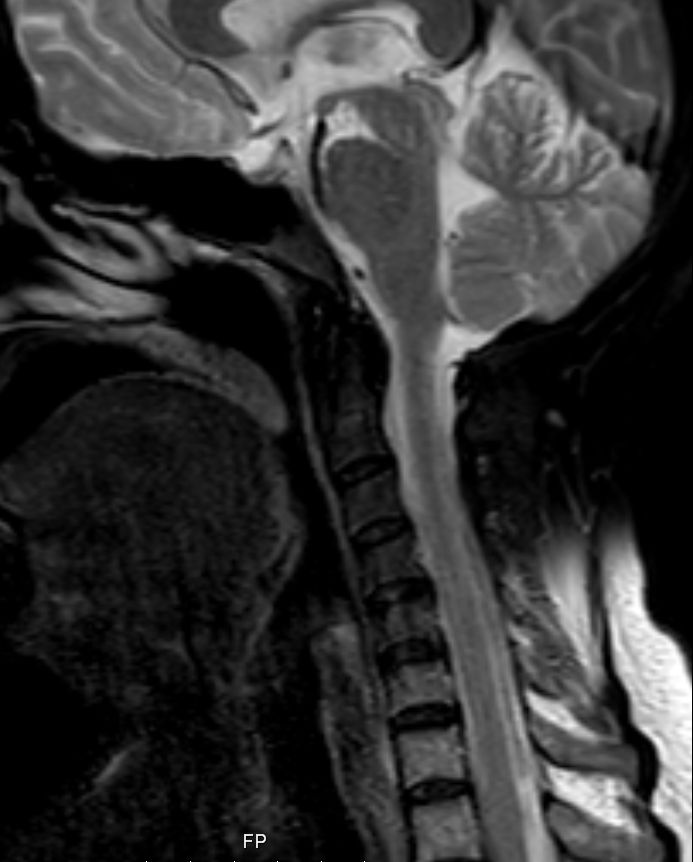

| Schädelbasis | 62-jährige Frau, bei der vor 2 Monaten ein Plattenepithelkarzinom der Zervix FIGO IIIB mit Radiochemotherapie behandelt wurde. Die Uterusgröße hatte von 13 auf 6 cm abgenommen. Jetzt Aufnahme mit der Diagnose Apoplex. | |||

Unklare Doppelkontur der Meningen des Halsmarks.![]() |

Ödem des rechten Temporallappens.![]() | |||